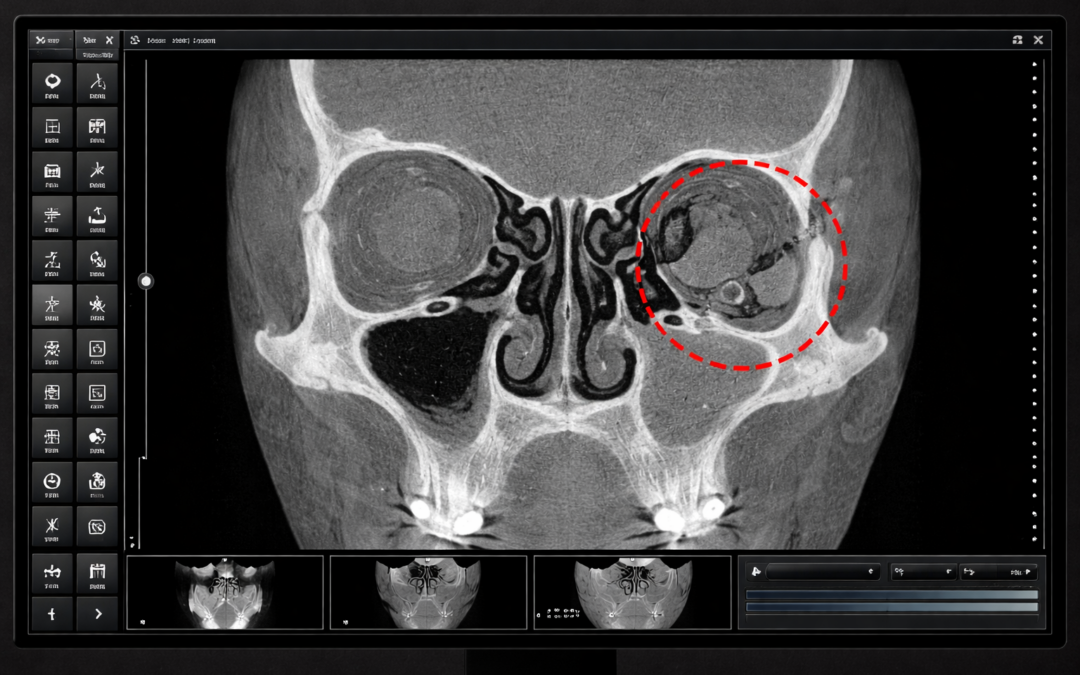

Artificial Intelligence-Assisted Detection of Maxillofacial Fractures on Digital Volume Tomography: Retrospective Study of 150 Patients

Yildirim A., Hertach R., and Yildirim V.

This retrospective study evaluated a deep learning-based AI model for detecting maxillofacial fractures on Digital Volume Tomography (DVT) in 150 patients. The AI achieved near-perfect accuracy (98%) and outperformed junior clinicians, while matching the performance of senior experts. These findings highlight AI’s potential to accelerate diagnosis, reduce missed fractures, and improve emergency trauma care workflows.